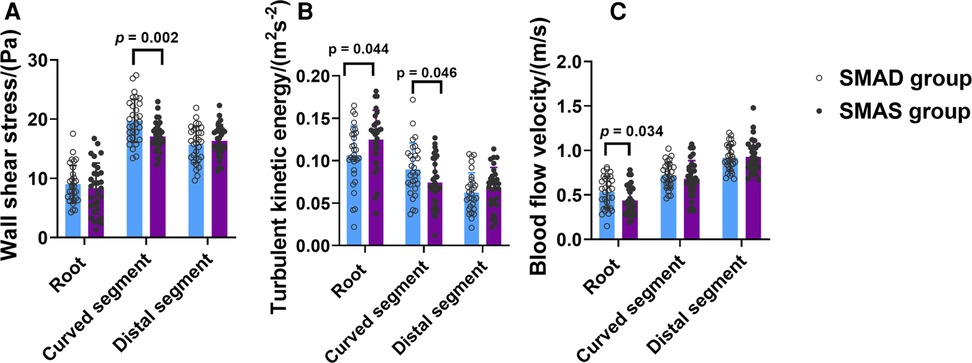

The SMAD group had higher WSS than the SMAS group in the curved segment (19.74 ± 3.63 pa vs. 17.09 ± 2.48 pa; p = .002); and the WSS in the curved segment was higher than in the other two segments in both groups. Compared with the SMAD group, the SMAS group had higher TKE in the root (0.125 ± 0.035 m2s−2 vs. 0.106 ± 0.035 m2s−2; p = .044) but lower TKE in the curved segment (0.090 ± 0.031 m2s−2 vs. 0.074 ± 0.029 m2s−2; p = 0.046); there was no difference between groups in the TKE of the distal segment. The TKE values in the root and the curved segment were higher than in the distal segment in both groups. The BFV in patients with SMAS was lower than in patients with SMAD in root (0.44 ± 0.16 m/s vs. 0.53 ± 0.18 m/s; p = 0.034); there was no difference between the groups in the BFV values in the other segments (Figure 4).

Figure 4. The comparison of hemodynamic parameters, including Wall shear stress (WSS) (A), turbulent kinetic energy (TKE) (B), and blood flow velocity (BFV) (C), in the three segments (root, curved and distal segment) of the superior mesenteric artery (SMA) in the superior mesenteric artery dissection (SMAD) and superior mesenteric atherosclerotic stenosis (SMAS) groups.